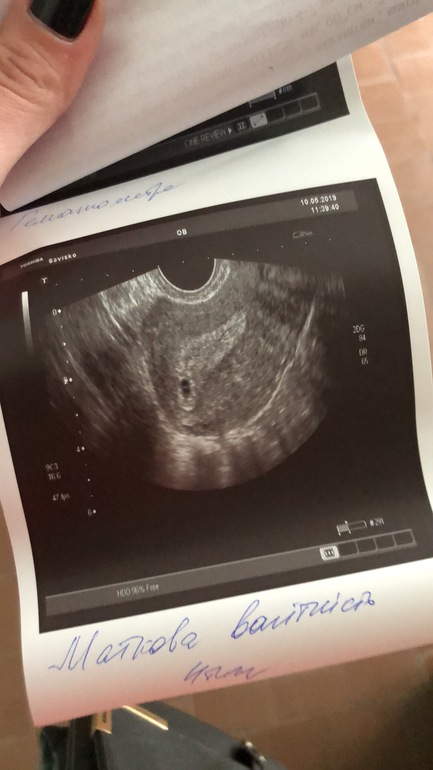

Вот и мы❤️

По узи пишет 4 недели(эмбриональные). Но по месячных 5 недель 2 дня.